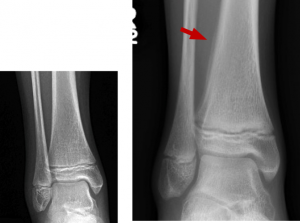

BELOW: Day 1 – normal

RIGHT: Week 3 – subtle periosteal reaction lateral aspect distal tibia